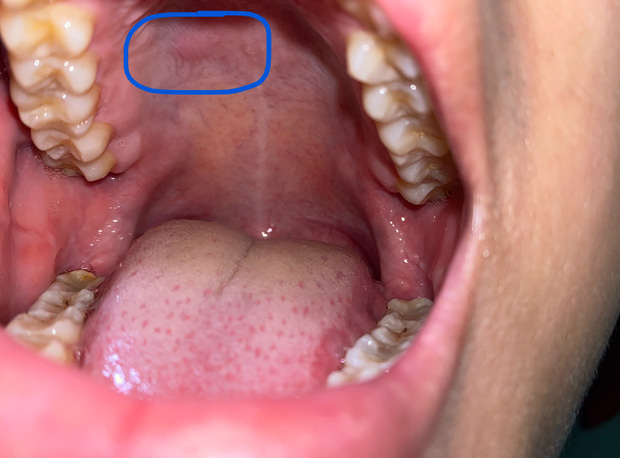

4. Thay đổi màu sắc của niêm mạc miệng

Niêm mạc miệng bình thường có màu hồng, nếu chuyển sang màu trắng, nâu hoặc đen nghĩa là tế bào biểu bì niêm mạc đã bị biến đổi. Đặc biệt, niêm mạc miệng sẽ còn trở nên thô ráp, dày lên hoặc không liền lại và xuất hiện bạch sản niêm mạc miệng hoặc ban đỏ, có thể trở thành ung thư sau đó.